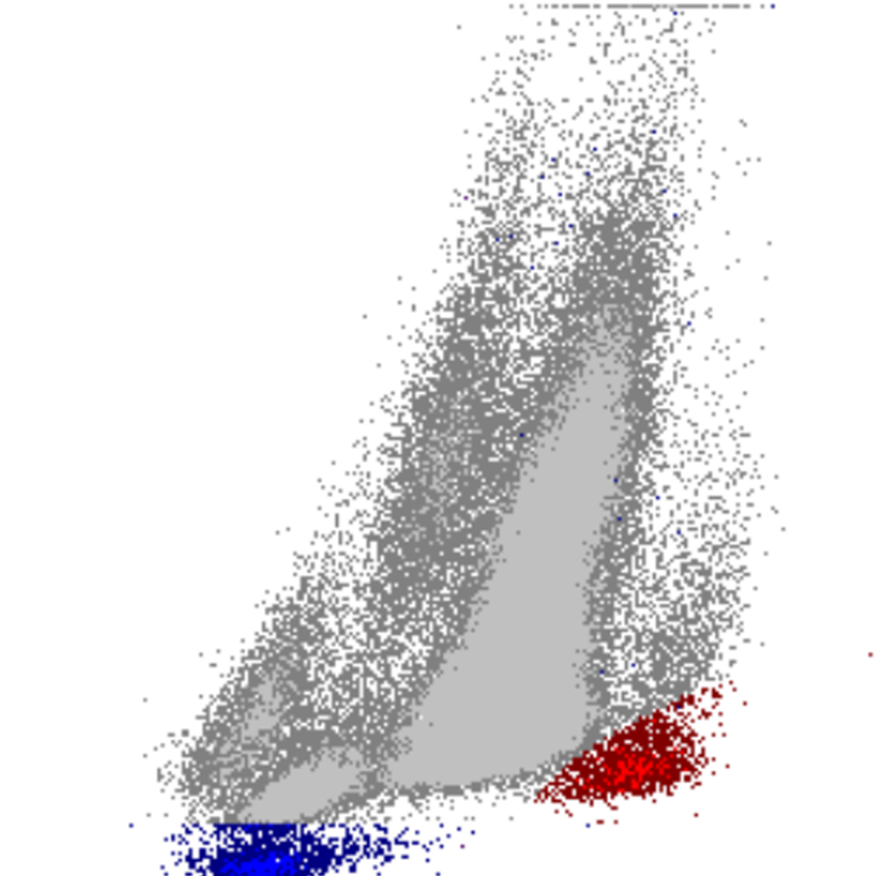

Densité

La densité des points dans un diagramme de dispersion reflète le nombre de cellules présentant des caractéristiques physiques et de fluorescence similaires. Le diagramme indique ainsi non seulement la présence de populations cellulaires, mais aussi leur taille relative et leur homogénéité.

• Une forte densité de points indique une population cellulaire importante et relativement homogène

• Des motifs diffus ou dispersés peuvent suggérer une hétérogénéité, une activation ou la présence de cellules anormales

• Des déplacements, un élargissement ou un chevauchement entre populations constituent souvent des signes précoces de morphologie anormale ou de cellules rares